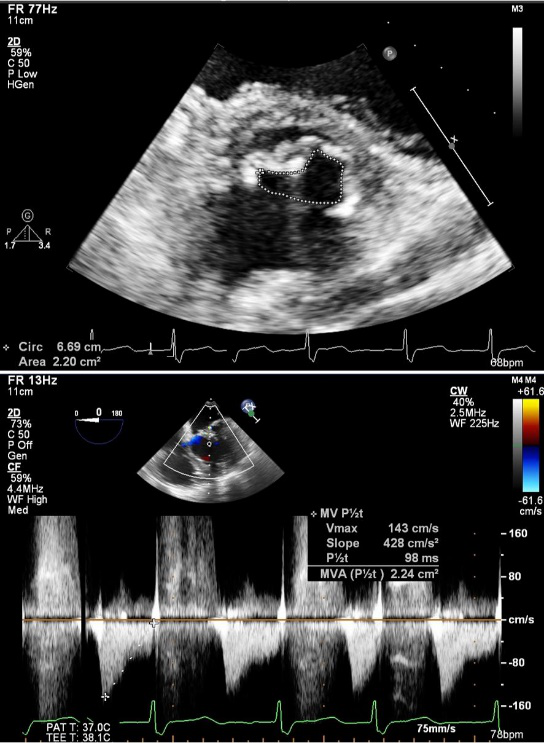

患者高龄,基础状态差,不适合外科手术;又因合并左房血栓,亦不适合常规PBMV术;但药物治疗仍症状明显。为解决患者这一困境,经团队讨论为患者量身定制了手术方案:颈动脉滤器脑保护+动静脉轨道+PBMV。手术在静脉复合麻醉、食道超声下进行。穿刺右侧股动静脉及左侧股动脉,经左侧股动脉入路成功于左右颈内动脉分别置入雅培颈动脉滤器进行脑保护(图2)

图2. 颈动脉滤器置入